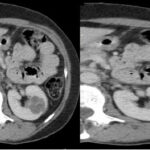

Fase corticomedular y arterial

Esta primera fase ocurre en los primeros 25 a 70 segundos posteriores a la inyección del medio de contraste; la corteza renal, al retener el medio de contraste en este tiempo en los capilares corticales aumenta de una manera intensa diferenciándose de la médula renal, que se encuentra hipodensa.

La fase arterial o corticomedular es esencial para la estadificación, extensión y planificación quirúrgica, si fuese el caso de la neoplasia encontrada, ya que ofrece un mejor detalle vascular (opacificación de los vasos), una mayor definición anatómica y de lesiones vascularizadas en el hígado, el bazo o el páncreas, consideradas dentro del contexto de una metástasis (Fig. 2).

Los errores diagnósticos que pueden presentarse durante esta fase se asocian a lesiones de pequeño tamaño; en el caso de un tumor hipervascularizado pequeño aumentaría su atenuación en la misma medida en que lo haría la corteza. Otro error que puede ocurrir es con los tumores pequeños que se localizan hacia la médula, ya que por su ubicación se mantendrían hipodensos durante esta fase 3-4.